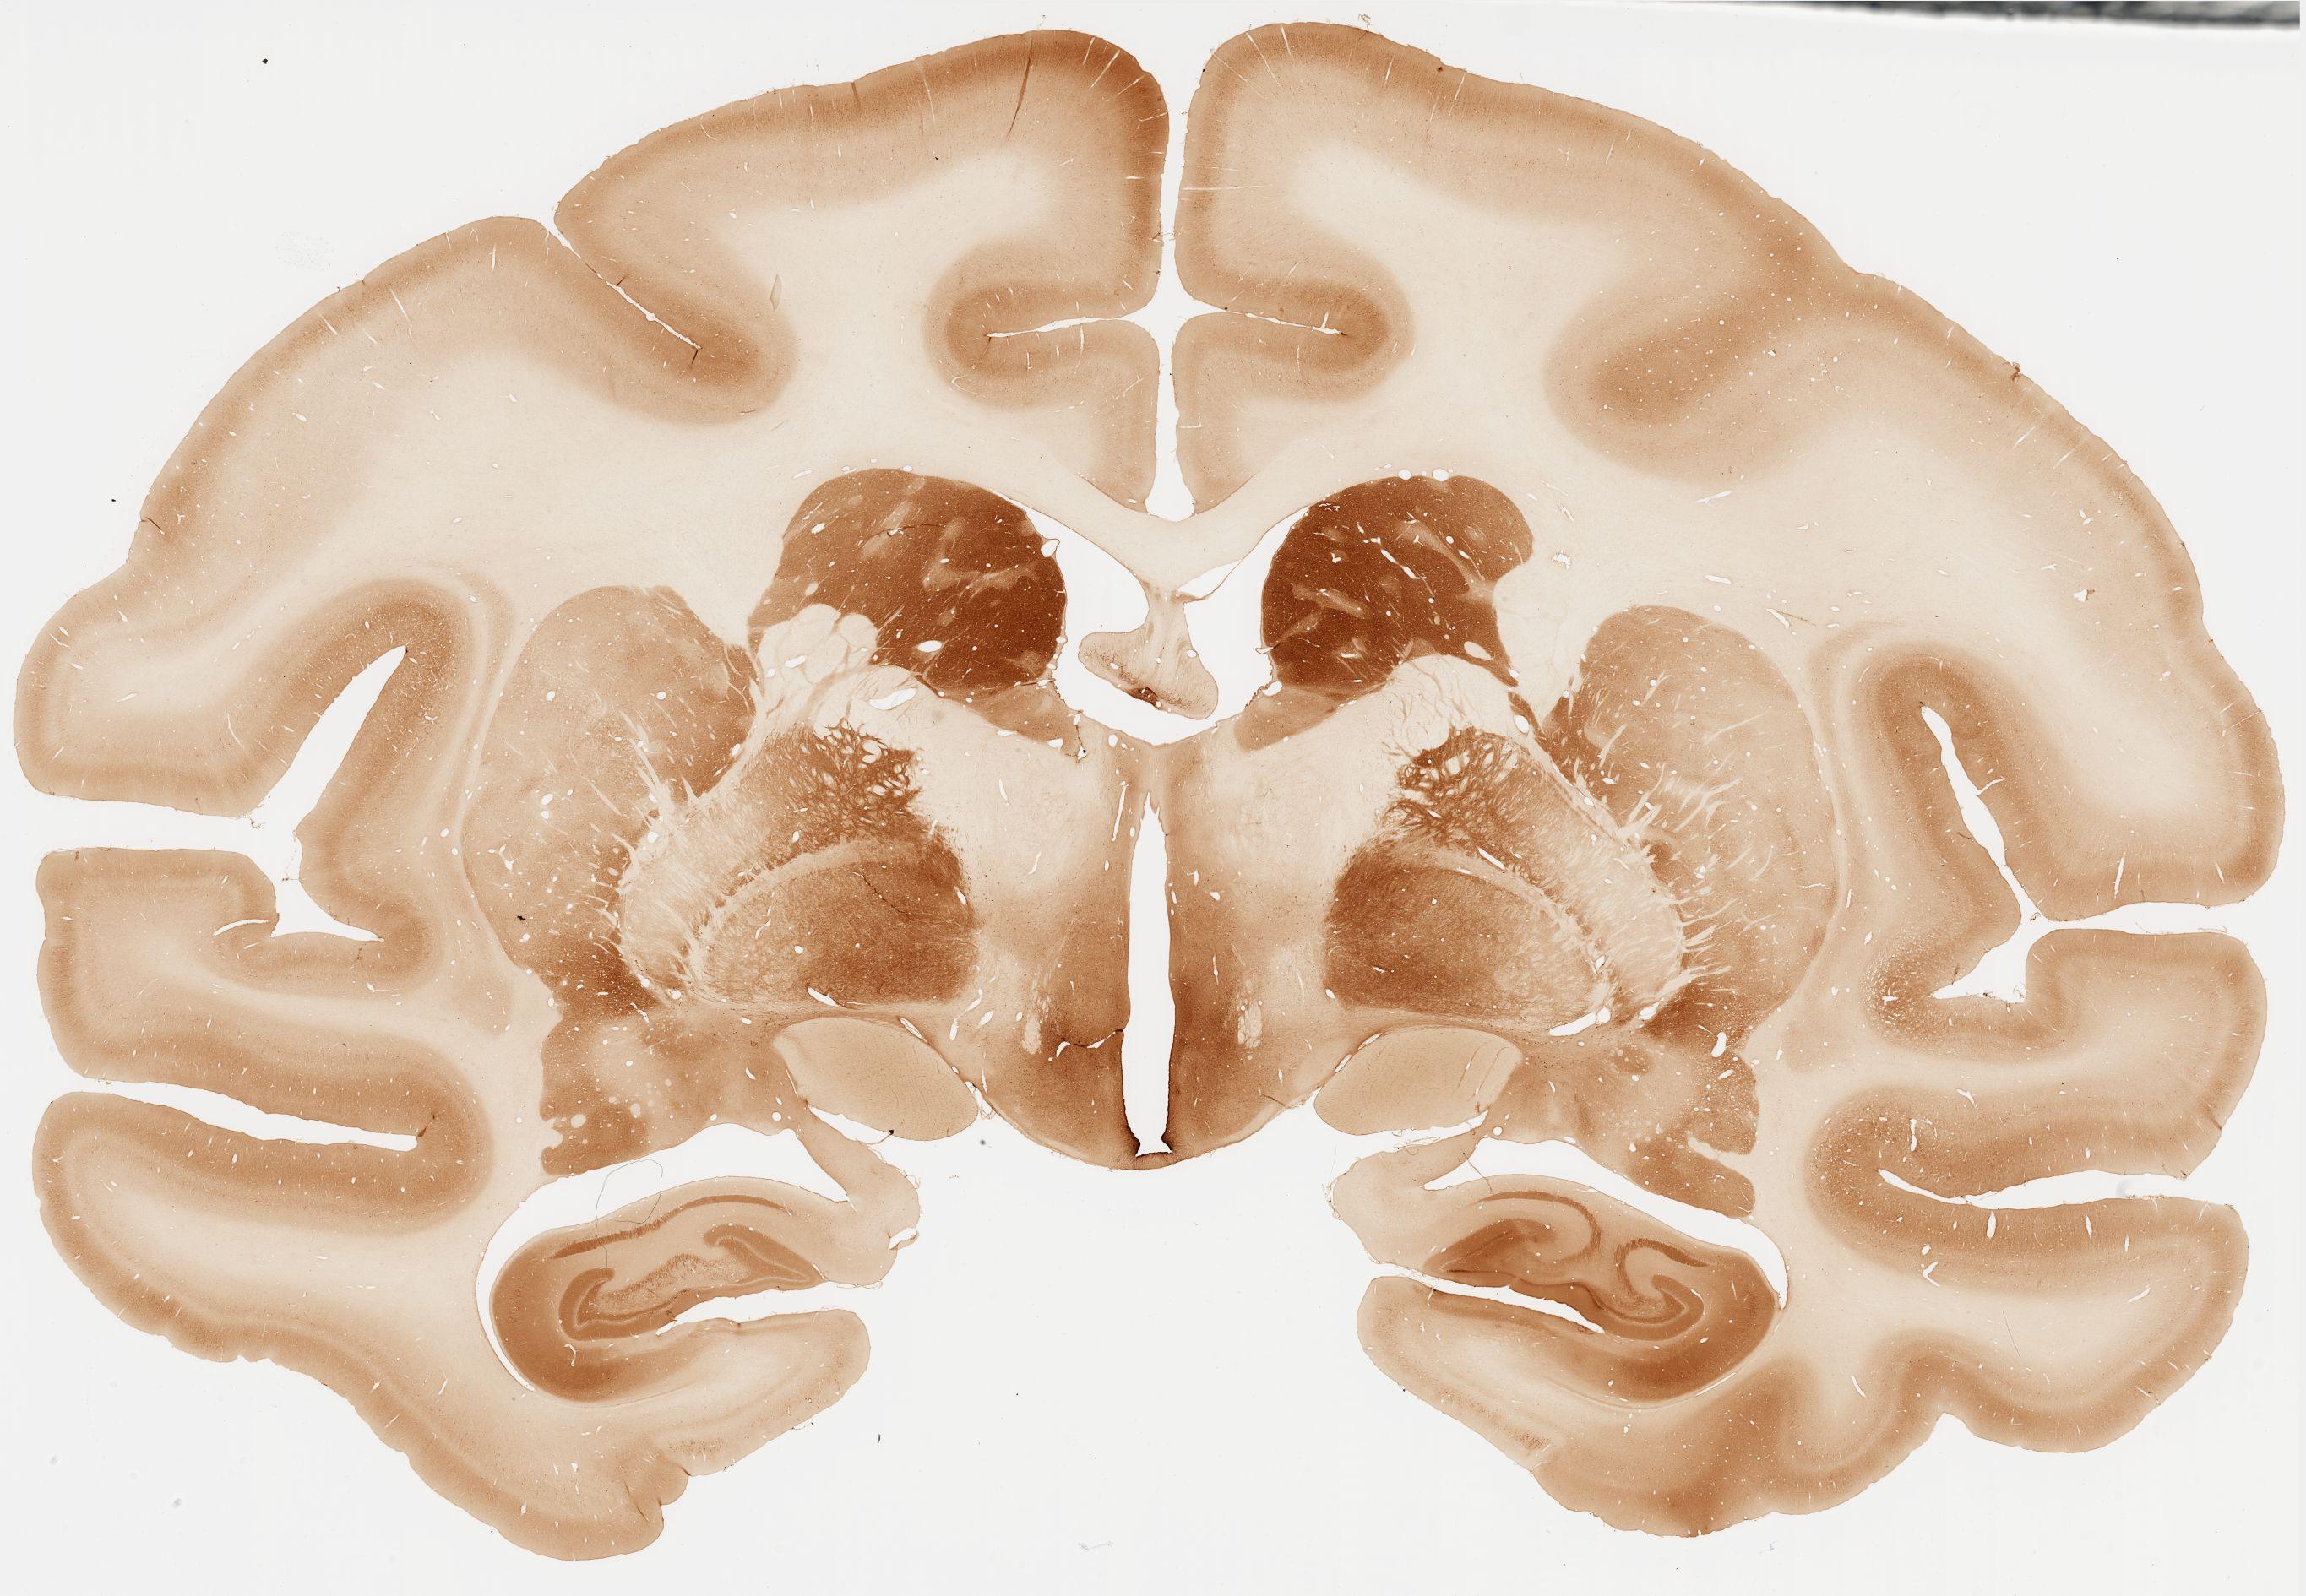

Datasets -> Macaca Fascicularis -> Calb, (Calbindin), coronal, immuno, Whole-Brain, adult

[ Metadata ]   ·   Source: Edward G. Jones

066